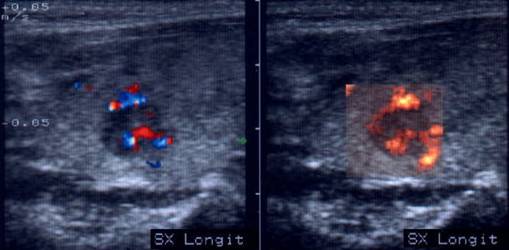

Lob stang, proiectie trasversala si longitudinala

Barbat de 55 ani. Formatiune nodulara voluminoasa ce ocupa 2/3 din lobul stang, hipoecogena, neomogenea, de 20 x 23 x 44mm(10 cc). Citoaspirata ecoghidata: carcinom midolar. Confirmat histologic.